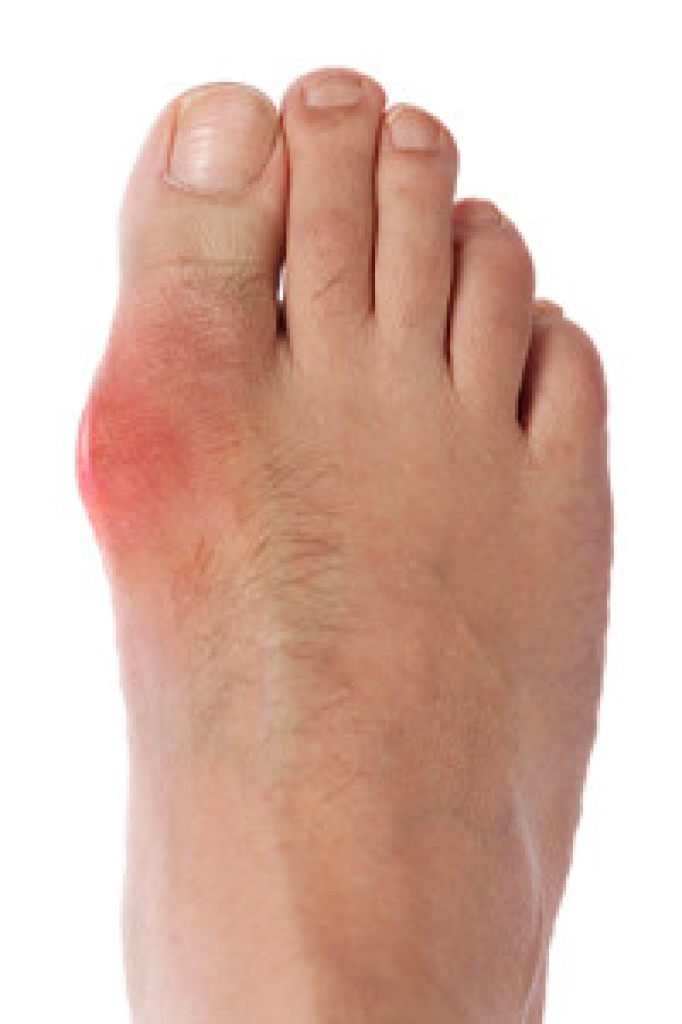

Gout